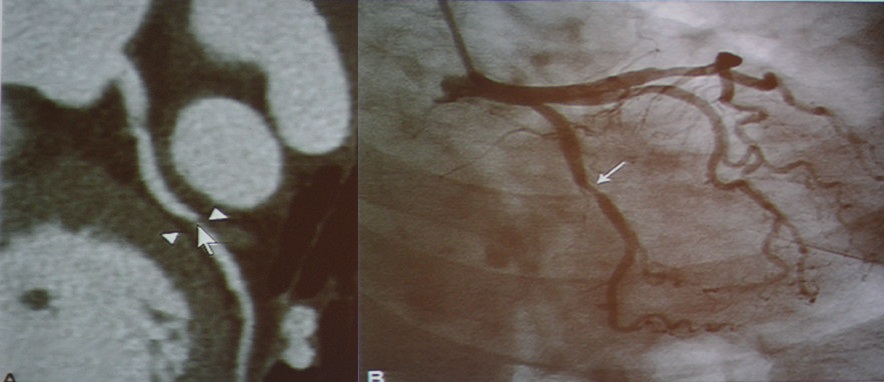

肺栓塞:CT可以准确地诊断肺栓塞。

图4-7 肺栓塞